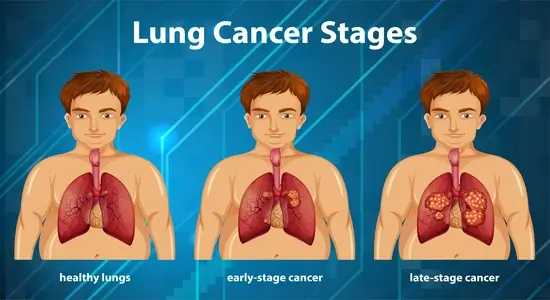

फेफड़ों के कैंसर के कितने चरण हैं?

कैंसर का चरण आपको बताता है, कि यह शरीर में कितनी दूर तक फैल चुका है और यह कितना गंभीर है। कैंसर के चरणों का निर्धारण डॉक्टरों को उपचार के उपयुक्त तरीके पर निर्णय लेने में मदद करता है। लेकिन, चरण निर्धारण का वर्णन करने का एक सीधा तरीका इस प्रकार है:

- स्थानीयकृत, जिसमें कैंसर फेफड़े तक ही सीमित होता है।

- क्षेत्रीय, जिसमें कैंसर छाती के भीतर लिम्फ नोड्स (या ग्रंथियों) में फैल गया है।

- दूरस्थ, जिसमें कैंसर शरीर के अन्य भागों में फैल गया है (या मेटास्टेसाइज़ हो गया है)।

- चरण I: कैंसर फेफड़ों में पाया जाता है, लेकिन यह फेफड़ों के बाहर नहीं फैला है।

- चरण II: कैंसर फेफड़ों और आस-पास के लिम्फ नोड्स में पाया जाता है।

- चरण III: कैंसर फेफड़ों और छाती के बीच में लिम्फ नोड्स में होता है।

- चरण IV: कैंसर दोनों फेफड़ों, फेफड़ों के आस-पास के हिस्से या दूर के अन्य अंगों में फैल गया है।